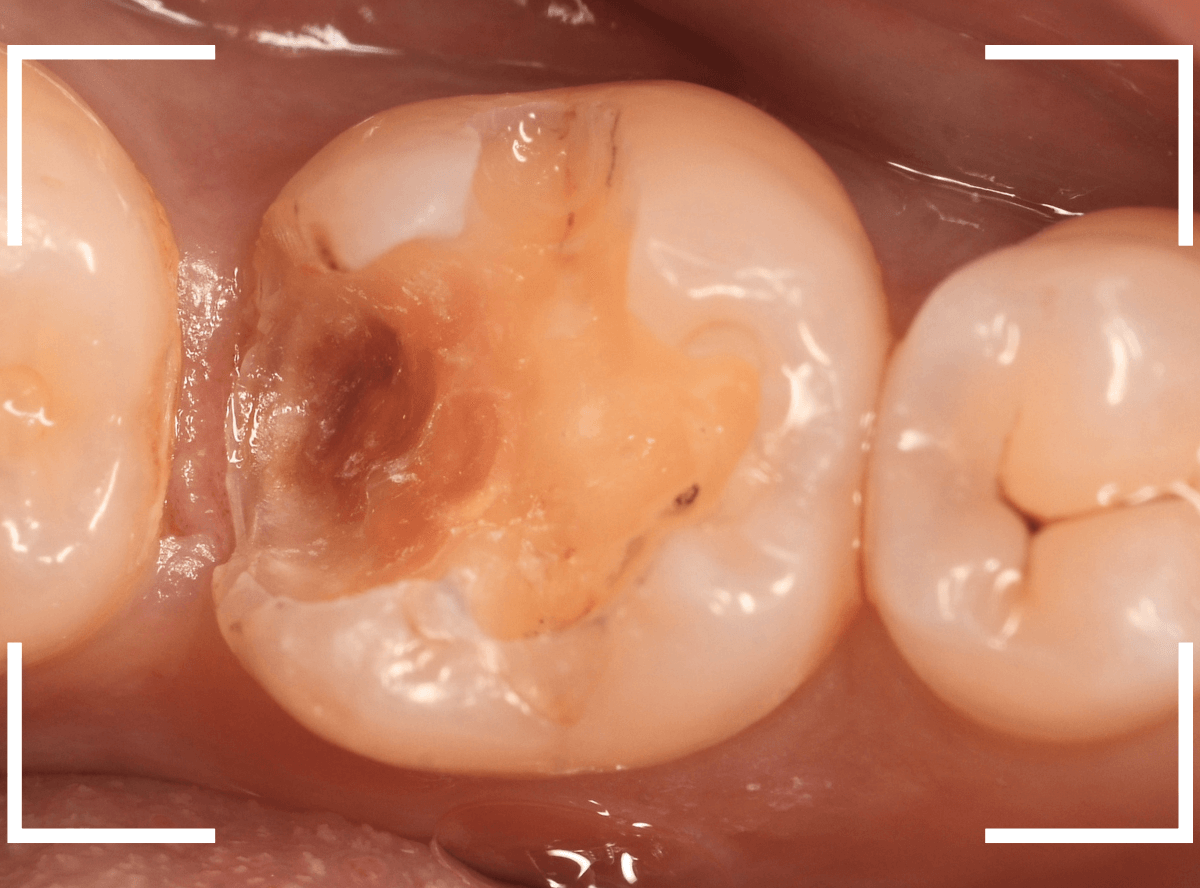

中のお薬も慎重に外して虫歯を除去します。

虫歯が深く、歯肉の下まで浸食していましたので、歯肉を部分切除し、虫歯を全て除去したところで、奇跡的に神経スレスレの状態でとどまっていました。

何とも言えませんが、神経を残せる可能性が出てきました。

虫歯が神経まで達していなくても、治療前から自発痛(何もしなくても痛い)があれば、神経をとらなければいけません。

今回は、そこまでの症状がありませんでしたので、患者さんと相談の上、神経を取らずに残す方法で様子を見る事になりました。

痛みが出ませんように。。。